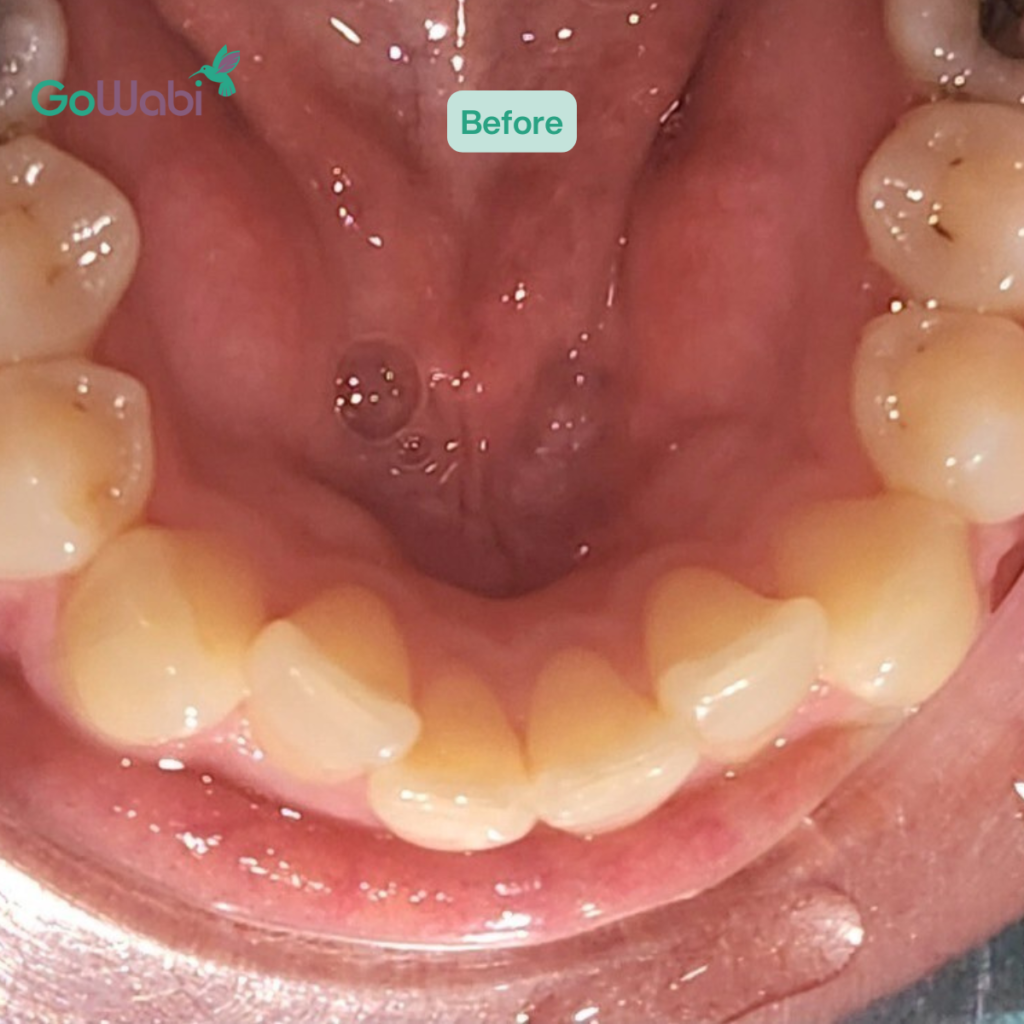

เปรียบเทียบผลลัพธ์ก่อน-หลังการจัดฟันใส Dr Clear Aligners ที่ DCA Dental Clinic

ก่อนทำ

- ฟันซ้อนเก บางซี่หมุนผิดทิศทาง

- ยิ้มแล้วไม่มั่นใจ รู้สึกว่าฟันไม่สวย